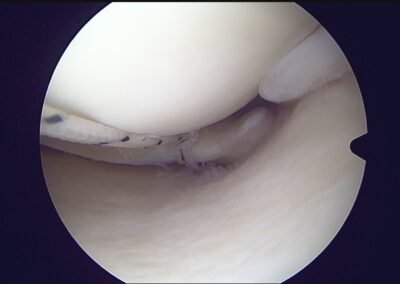

GalleryShoulder rotator cuff repair Meniscus root repair Meniscus repair Bankart repair for recurrent shoulder dislocation ACL reconstruction Machines Instruments